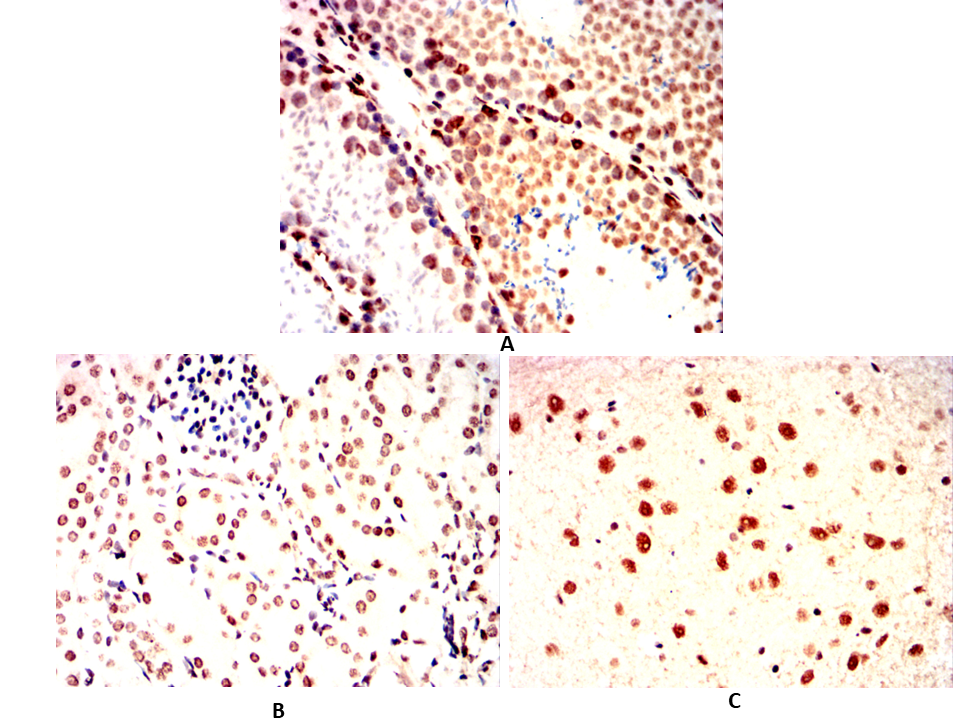

Immunohistochemical analysis of paraffin-embedded Mouse testicles(A)Mouse kidney(B)Mouse cerebellum(C) using ESR1 mouse mAb with DAB staining.